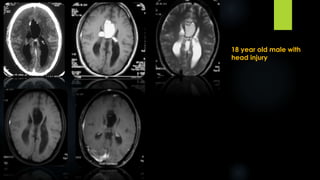

18 year old male with

head injury

Intracranial Lipoma (contd.)

 Incidence- 0.1-0.5% of primary brain tumours.

 5% of corpus callosum tumors

 Neither age nor gender related

 Location- at or near midline- 80-95%. Common sites are pericallosal area, quadrigeminal,

interpeduncular, chiasmatic, sylvian cisterns, cerebellopontine angle.

 CT- very low density mass(-50 to-100 HU), curvilinear or nodular calcification. With

ass.congenital malformations.

 Show no enhancement

 MRI- Hyperintense on both T1W & fast spin-echo T2WI. Low signal foci represent calcification,

traversing arteries or nerves.

 Fat- suppression technique used to confirm diagnosis.